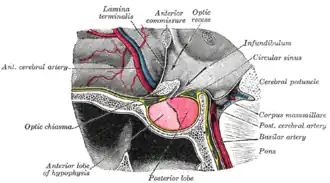

Localizada na base do crânio, a hipófise é protegida por uma estrutura óssea chamada sela túrcica. | |

Diagrama de um corte sagital mediano através da hipófise de um macaco adulto. | |

Hipófise (também denominada glândula pituitária) é uma glândula endócrina com cerca de 1 cm de diâmetro alojada na sela túrcica (A sela turca protege a hipófise, mas deixa um espaço bem pequeno para expansão) ou fossa hipofisária do osso esfenoide na base do cérebro. Está localizada abaixo do hipotálamo e posteriormente ao quiasma óptico, sendo ligada ao hipotálamo pela haste pedúnculo hipofisário ou infundíbulo, é envolvida pela dura-máter (exceto o infundíbulo). A hipófise é considerada uma "glândula mestra", pois secreta hormônios que controlam o funcionamento de outras glândulas, sendo grande parte de suas funções reguladas pelo hipotálamo.